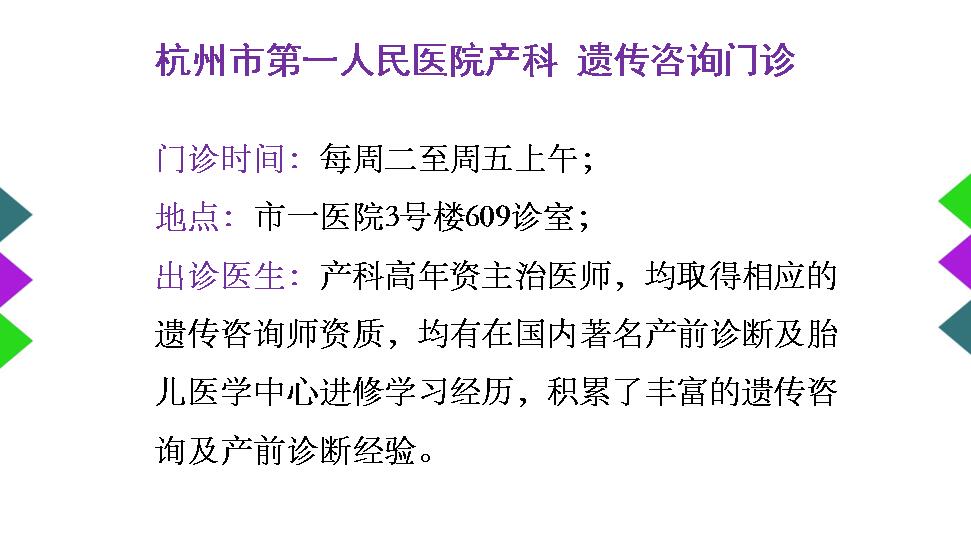

3. 遗传咨询门诊

为产前筛查高风险孕妇提供咨询和产前诊断服务。

预约挂号://guahao.zjol.com.cn/department/0571057101/1502